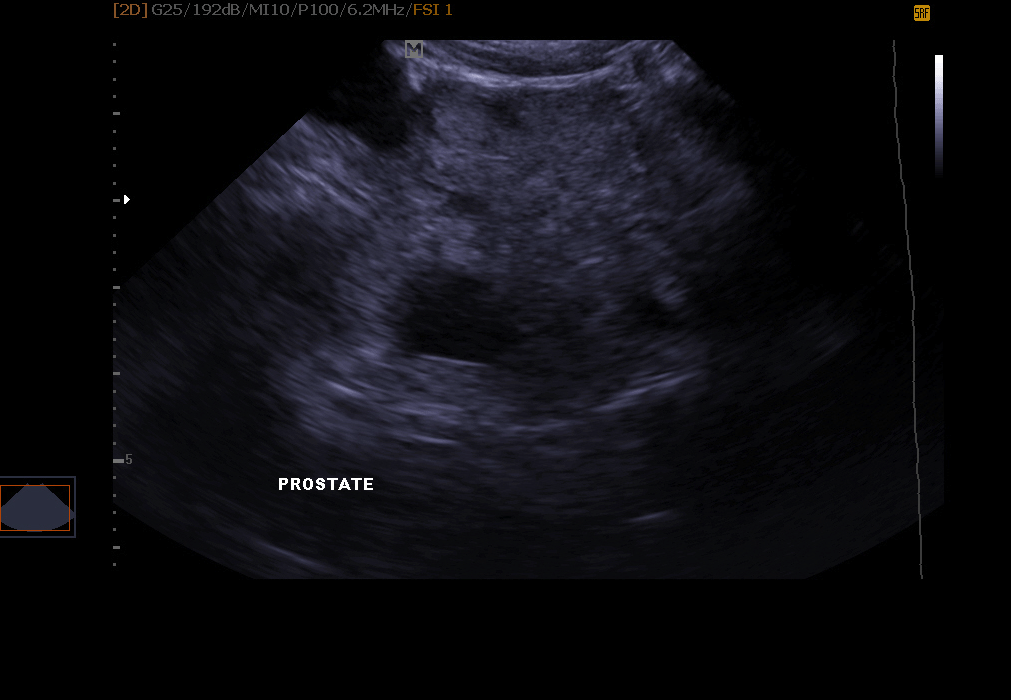

Examen de l’appareil génital: infection de l’utérus, gestation détectable dés 18 à 21 jours chez la chatte et la chienne, kystes ovariens, exploration de la prostate chez le mâle.